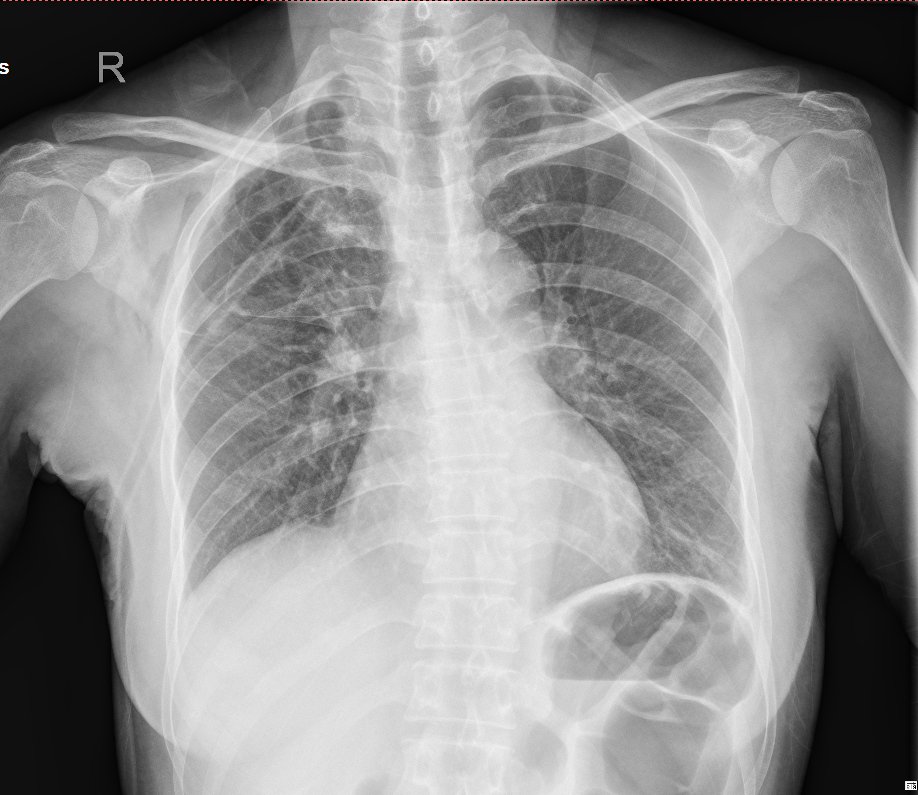

手术过程非常顺利,术后恢复迅速。术后第一天李女士便能下床活动,第二天停用所有药物。而后复查胸片恢复效果良好,拔除胸腔引流管,且手术创伤小,引流少,不漏气,无咳血和并发症状。手术后第四天李女士便顺利出院,她的生活重回正轨。